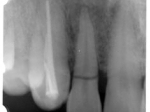

片側2歯欠損片側2歯欠損片側2歯欠損 主訴-入れ歯を使ってみたが違和感強くてダメ。固定のものにしたい。術前下顎口腔内(鏡像) 二次オペ時(鏡像)二次オペ時(鏡像)二次オペ時(鏡像) 術後術後術後、左下奥2本インプラント(鏡像) 術後(レントゲン)術後(レントゲン)術後(レントゲン)、左下奥2本インプラント